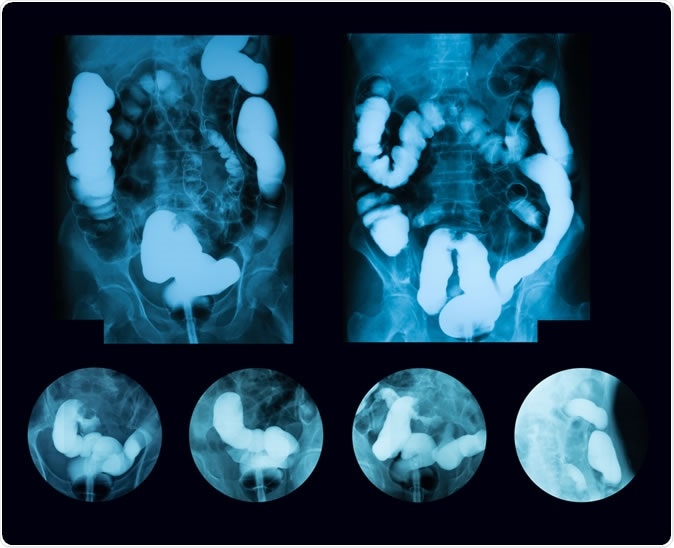

Barium enema double contrast, case of sigmoid colon cancer (Inflammatory Bowel Disease: IBD). Image Credit: Suttha Burawonk / Shutterstock